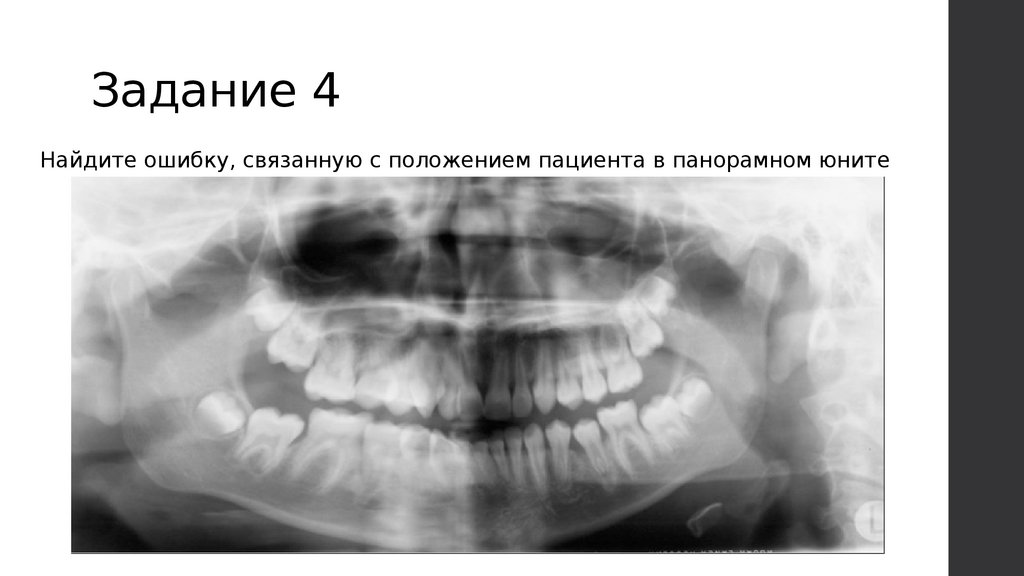

Задание 4

Найдите ошибку, связанную с положением пациента в панорамном юните